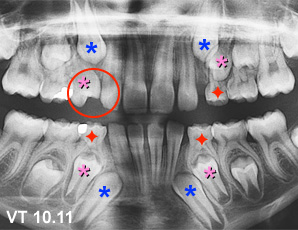

Cas VT : La première molaire temporaire supérieur droite est tombée de façon précoce ce qui a accéléré l’éruption de la prémolaire qui empiète maintenant sur l’espace réservé à la canine . La prémolaire est presque en contact avec l’incisive latérale (cercle). Il serait indiqué d’extraire les autres premières molaires temporaires restantes (étoiles rouge)pour aider l’éruption des autres premières prémolaires. (Voir la légende pour identifier les dents)